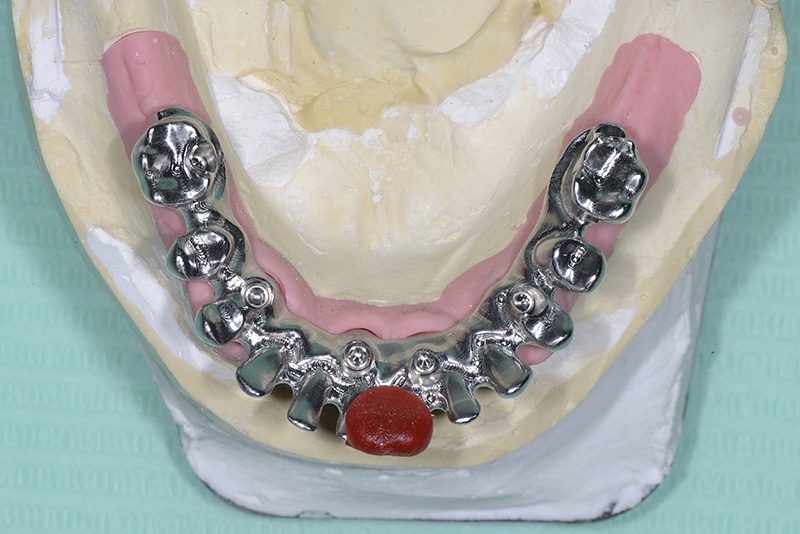

Vengono utilizzati 2 tipi di provvisori: il primo, cementato ai denti vicini, viene utilizzato dal momento dell’estrazione del dente fino ad impianto osteointegrato (circa 6 mesi); il secondo, avvitato direttamente all’impianto, ha una funzione di prova estetica ma soprattutto di guida per la maturazione dei tessuti gengivali peri-implantari portandoli verso la maturazione completa prima di posizionare la corona finale in disilicato di litio.